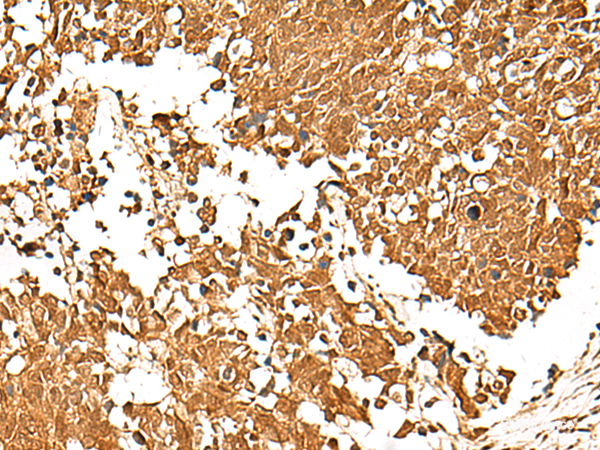

This gene encodes a member of the T-cell factor/lymphoid enhancer-binding factor family of high mobility group (HMG) box transcriptional activators. This gene is expressed predominantly in T-cells and plays a critical role in natural killer cell and innate lymphoid cell development. The encoded protein forms a complex with beta-catenin and activates transcription through a Wnt/beta-catenin signaling pathway. Mice with a knockout of this gene are viable and fertile, but display a block in T-lymphocyte differentiation. Alternative splicing results in multiple transcript variants. Naturally-occurring isoforms lacking the N-terminal beta-catenin interaction domain may act as dominant negative regulators of Wnt signaling. Protein function: Transcriptional activator involved in T-cell lymphocyte differentiation. Necessary for the survival of CD4(+) CD8(+) immature thymocytes. Isoforms lacking the N-terminal CTNNB1 binding domain cannot fulfill this role. Binds to the T-lymphocyte-specific enhancer element (5'-WWCAAAG-3') found in the promoter of the CD3E gene. May also act as feedback transcriptional repressor of CTNNB1 and TCF7L2 target genes. TLE1, TLE2, TLE3 and TLE4 repress transactivation mediated by TCF7 and CTNNB1. [The UniProt Consortium]